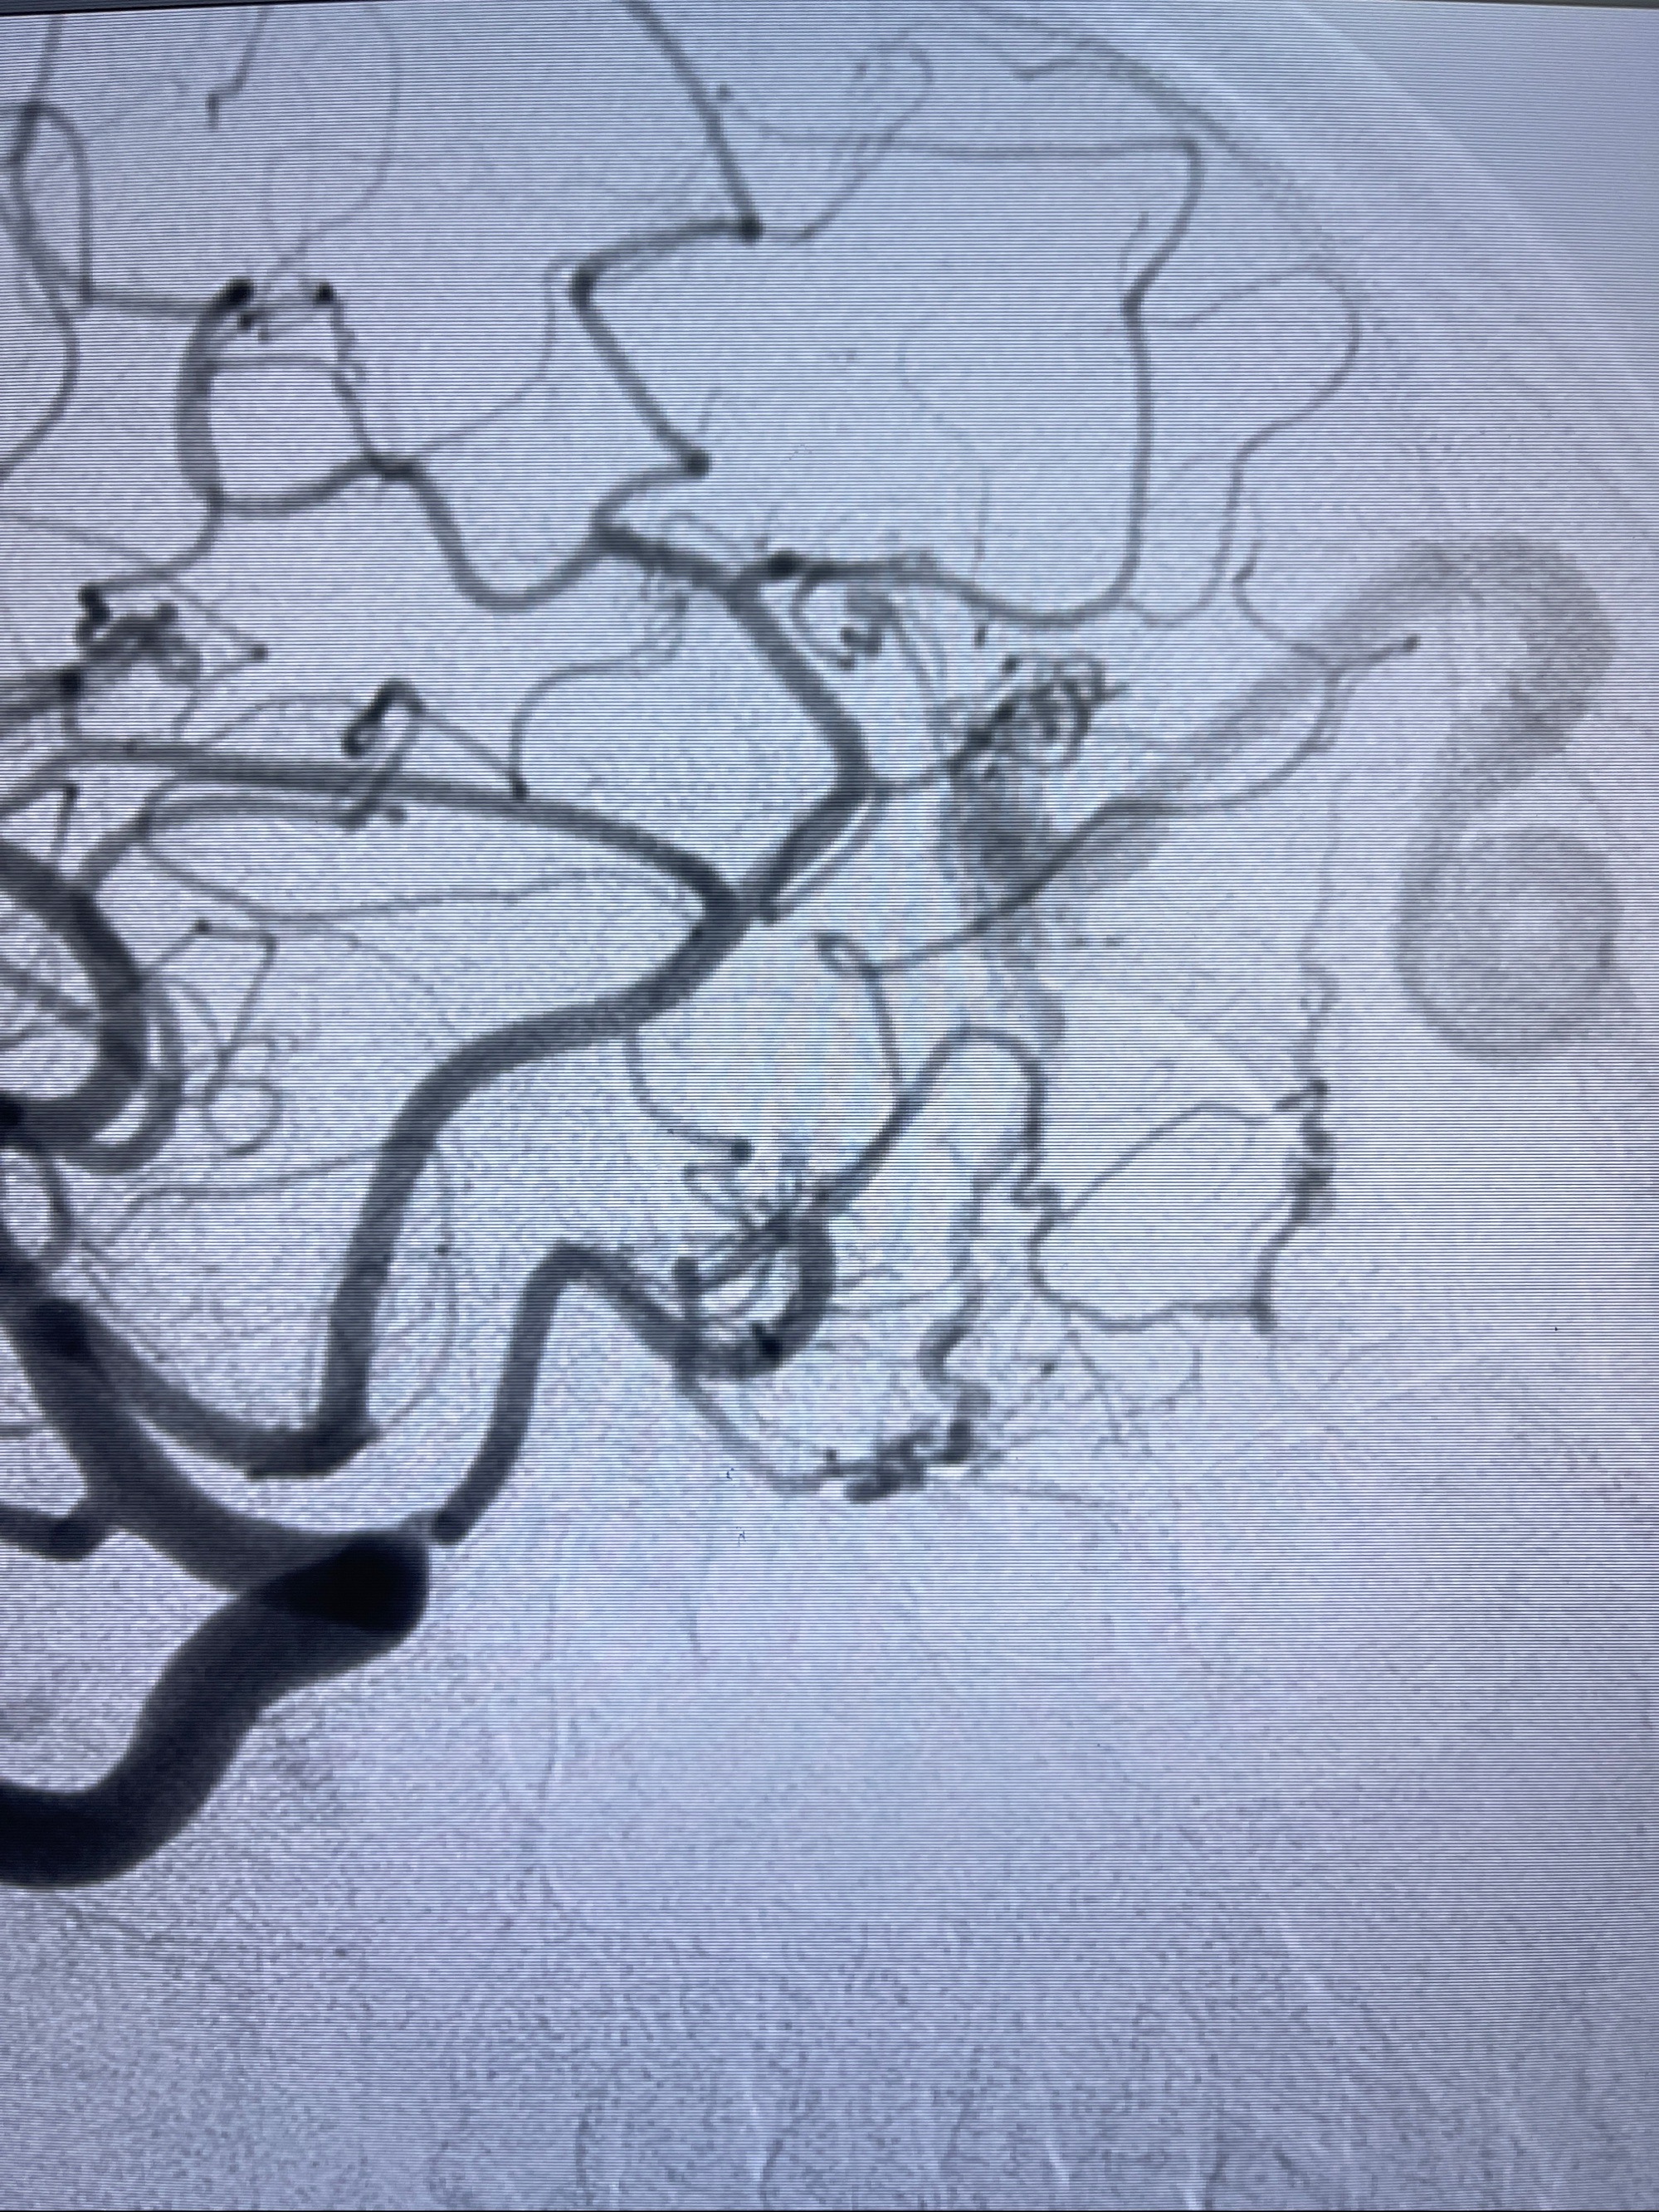

2023-09-13全脑血管造影:前颅底硬脑膜动静脉瘘,供血动脉为双侧胼周动脉、眼动脉脑膜支,静脉向上矢状窦方向引流

治疗策略:

- 外科手术?

- 介入干预:静脉途径栓塞or动脉途径填塞?